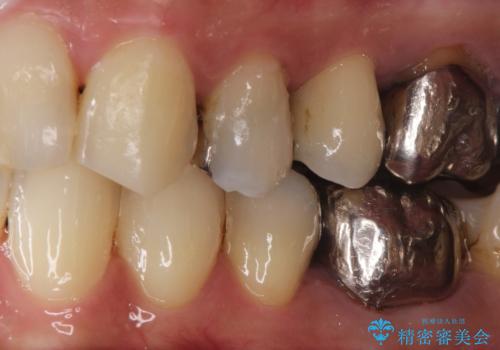

大きい虫歯 根管治療〜オールセラミッククラウン

- 大きな虫歯を認めた患者様です。

自発痛を認めたことから、不可逆性歯髄炎の診断を行い治療を介入しております。

根管治療した場合は速やかに被せ物による修復が必要です。